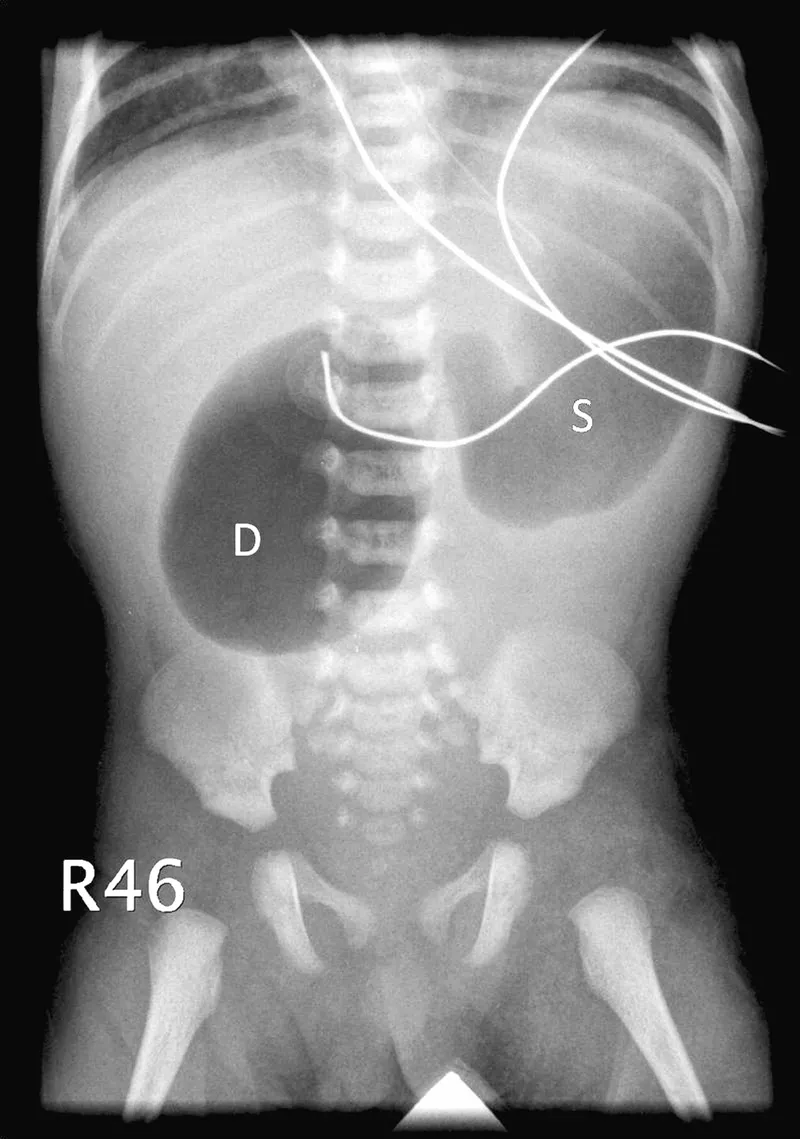

- X-ray: Classic "double bubble" sign (stomach and proximal duodenum).

- Absence of distal gas (indicates complete obstruction).

- Plain abdominal X-ray (e.g., "double bubble" sign).

- Duodenal atresia is strongly associated with Down syndrome and presents with a classic "double bubble" sign on X-ray.